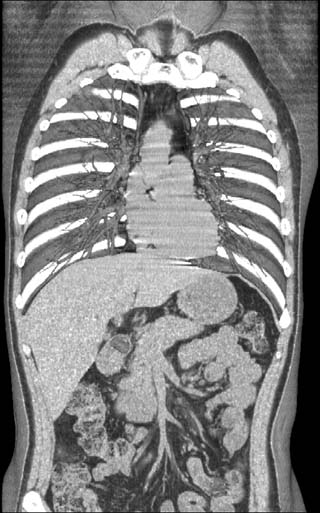

Clinical example #1

Chest-Abdomen / Voluntieer

1mmx8, pitch10